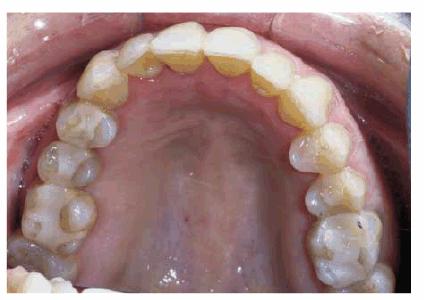

Figure 29-1K: Note the crowding of the mandibular anterior teeth.

Figure 29-1L: The teeth are less crowded, and the new tooth-colored restorations have been placed.

Figure 29-1M: The maxillary arch shows anterior crowding and defective amalgam restorations.

Figure 29-1N: Following 12 months of orthodontic treatment, the patient's amalgam restorations were replaced with posterior composite resin.

Figure 29-1O: Interdisciplinary 949o141j therapy including orthodontics, periodontics, and restorative dentistry combined to produce this attractive result 2 years following the initiation of treatment in this now younger-looking 78-year-old lady.